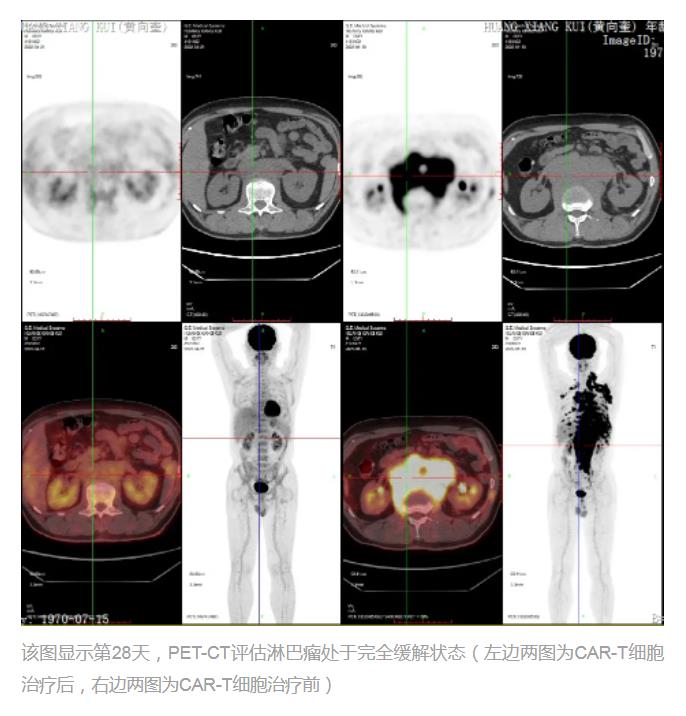

战胜血液系统癌症的新“武器”CAR-T细胞疗法